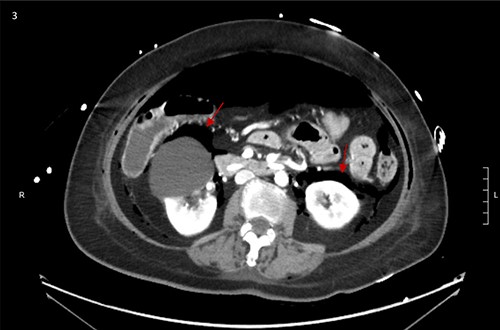

CT scan showed small bilateral pneumothoraces (Fig. 1a) in the setting of several mildly displaced anterior rib fractures with associated subcutaneous emphysema (Fig. 1b), as well as extensive intraperitoneal (Fig. 2), extraperitoneal and retroperitoneal (Fig. 3) air. However, imaging was negative for evidence of perforation. Given concern for abdominal compartment syndrome as evidenced by abdominal distension on exam, initially elevated peak pressures to 24 immediately following intubation, and CT findings of pneumoperitonum, the General Surgery service was consulted for evaluation and further assistance with management. On clinical exam, the patient’s abdomen was distended without tenderness, guarding, or rebound. Laboratory results were notable for white blood cell count of 21.1 per mm3, platelet count of 314 per mm3, and a whole blood lactate of 8.1 mmol/l. Her leukocytosis, though only mildly increased from her baseline of 15 over the previous days, was attributed to known Staphylococcus bacteremia for which she was on antibiotic therapy with a contribution from her shock and PEA arrest. Given the patient was hemodynamically stable with no signs of an acute abdomen, we decided to manage with serial abdominal exams without operative intervention. The patient was closely followed over the subsequent 5 days, during which time she remained stable; she no longer required pressors and was weaned to trach collar on post-arrest Day 2; her white blood cell count continued to downtrend and normalized post-arrest Day 7 as she remained on antibiotic therapy; no additional abdominal imaging was obtained, given her very benign abdominal exam. Operative management was never utilized and she remained asymptomatic. While in the intensive care unit, the patient improved and she was able to engage in physical and occupational therapy despite the pneumothoraces. She was discharged to a long-term acute care hospital on hospital Day 36.

Bilateral retroperitoneal air surrounding right and left kidneys.